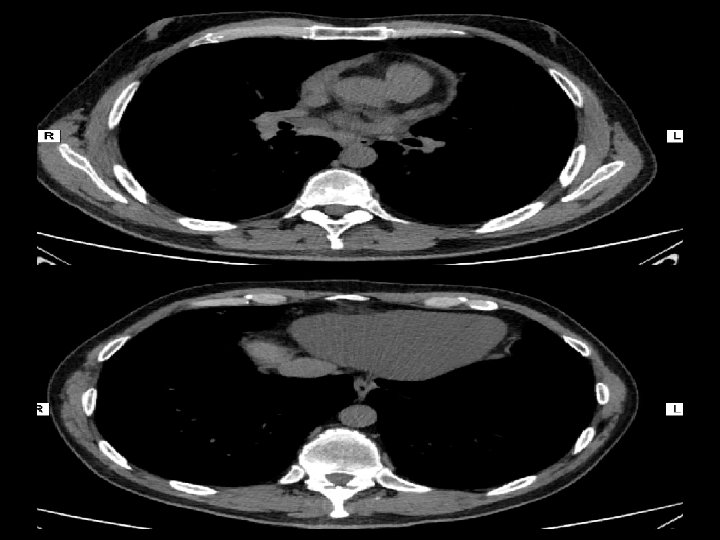

En ambos hemitórax se observan múltiples imágenes nodulillares de escasos milímetros de distribución difusa, predominando en los lóbulos superiores, de localización aleatoria En topografía del LM se observan aisladas prominencias bronquiales con sutiles cambios inflamatorios peribronquiales sin evidencia de consolidación. Pequeñas imágenes ganglionares a nivel supraclavicular en rango no adenopático. En topografía del espacio paratraqueal derecho y espacio subcarinal así como también a nivel hiliar bilateral se observan pequeñas imágenes ganglionares algunas con calcificaciones en su superficie de corte. Derrame pericárdico.

Forma crónica Caracteristicas radiológicas • • Linfoadenopatías hiliares bilaterales opacidades reticulonodulillares difusas en lóbulos medios y superiores

Adenopatías hiliares opacidades nodulares difusas con nódulos más grandes en las zonas pulmonares superiores

Imágenes características en tc: • Pequeños nódulos parenquimatosos distribuidos predominantemente en región peribroncovascular o en septos interlobulillares ( + frec ) • Engrosamiento septal interlobulillar(50%) • Adenopatías mediastinales (39%) • Engrosamiento paredes bronquiales (46%) • Opacidades en vidrio esmerilado (32%) • Patrón en panal de abeja (7%)

Linfoadenopatía hiliar Adenopatía mediastínica